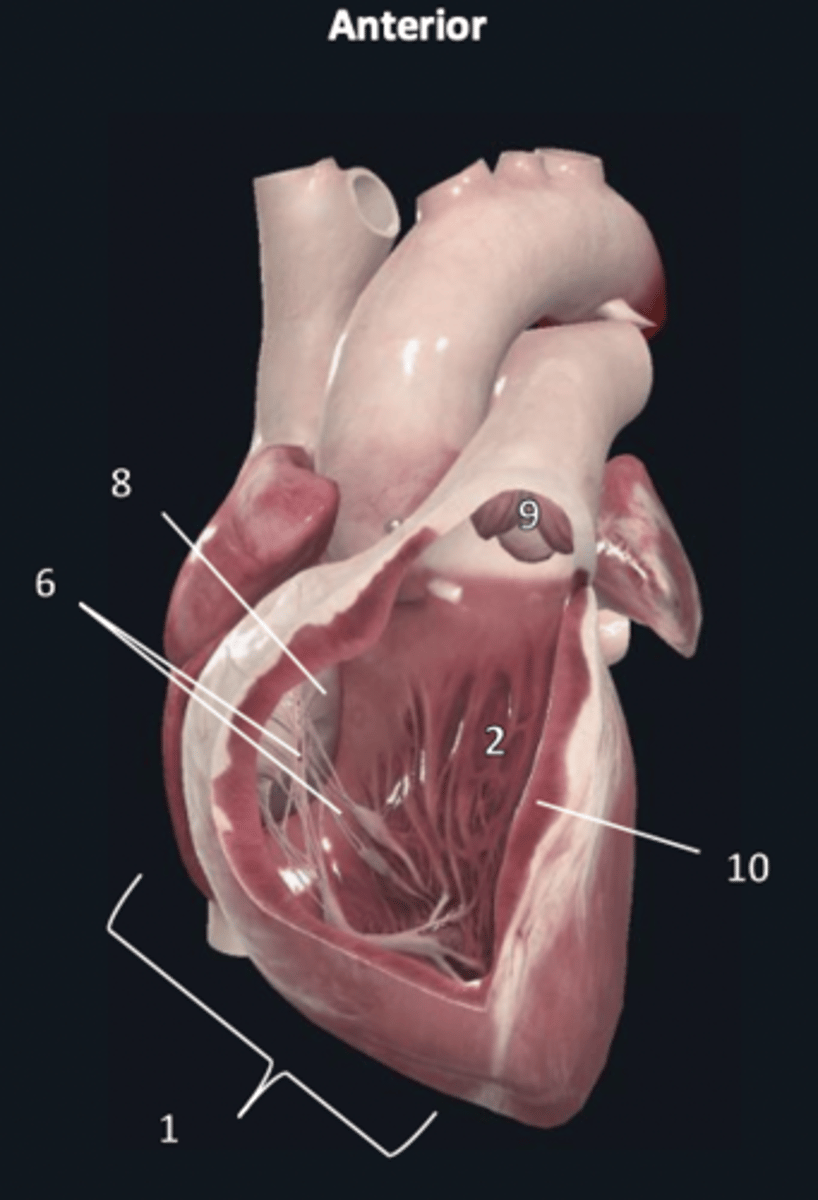

right ventricle

1

trabeculae carneae

2

septal papillary muscle

3

anterior papillary muscle

4

inferior papillary muscle

5

chordae tendineae

6

moderator band

7

tricuspid valve

8

pulmonary semilunar valve

9

interventricular septum

10